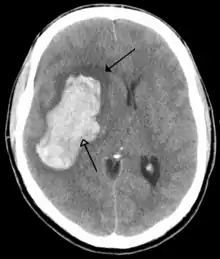

Tumours

Brain tumours can be either benign or cancerous. Most malignant tumours arise from another part of the body, most commonly from the lung, breast and skin.[177] Cancers of brain tissue can also occur, and originate from any tissue in and around the brain. Meningioma, cancer of the meninges around the brain, is more common than cancers of brain tissue.[177] Cancers within the brain may cause symptoms related to their size or position, with symptoms including headache and nausea, or the gradual development of focal symptoms such as gradual difficulty seeing, swallowing, talking, or as a change of mood.[177] Cancers are in general investigated through the use of CT scans and MRI scans. A variety of other tests including blood tests and lumbar puncture may be used to investigate for the cause of the cancer and evaluate the type and stage of the cancer.[177] The corticosteroid dexamethasone is often given to decrease the swelling of brain tissue around a tumour. Surgery may be considered, however given the complex nature of many tumours or based on tumour stage or type, radiotherapy or chemotherapy may be considered more suitable.[177]

Some treatments for stroke are time-critical. These include clot dissolution or surgical removal of a clot for ischaemic strokes, and decompression for haemorrhagic strokes.[195][196] As stroke is time critical,[197] hospitals and even pre-hospital care of stroke involves expedited investigations – usually a CT scan to investigate for a haemorrhagic stroke and a CT or MR angiogram to evaluate arteries that supply the brain.[194] MRI scans, not as widely available, may be able to demonstrate the affected area of the brain more accurately, particularly with ischaemic stroke.[194]